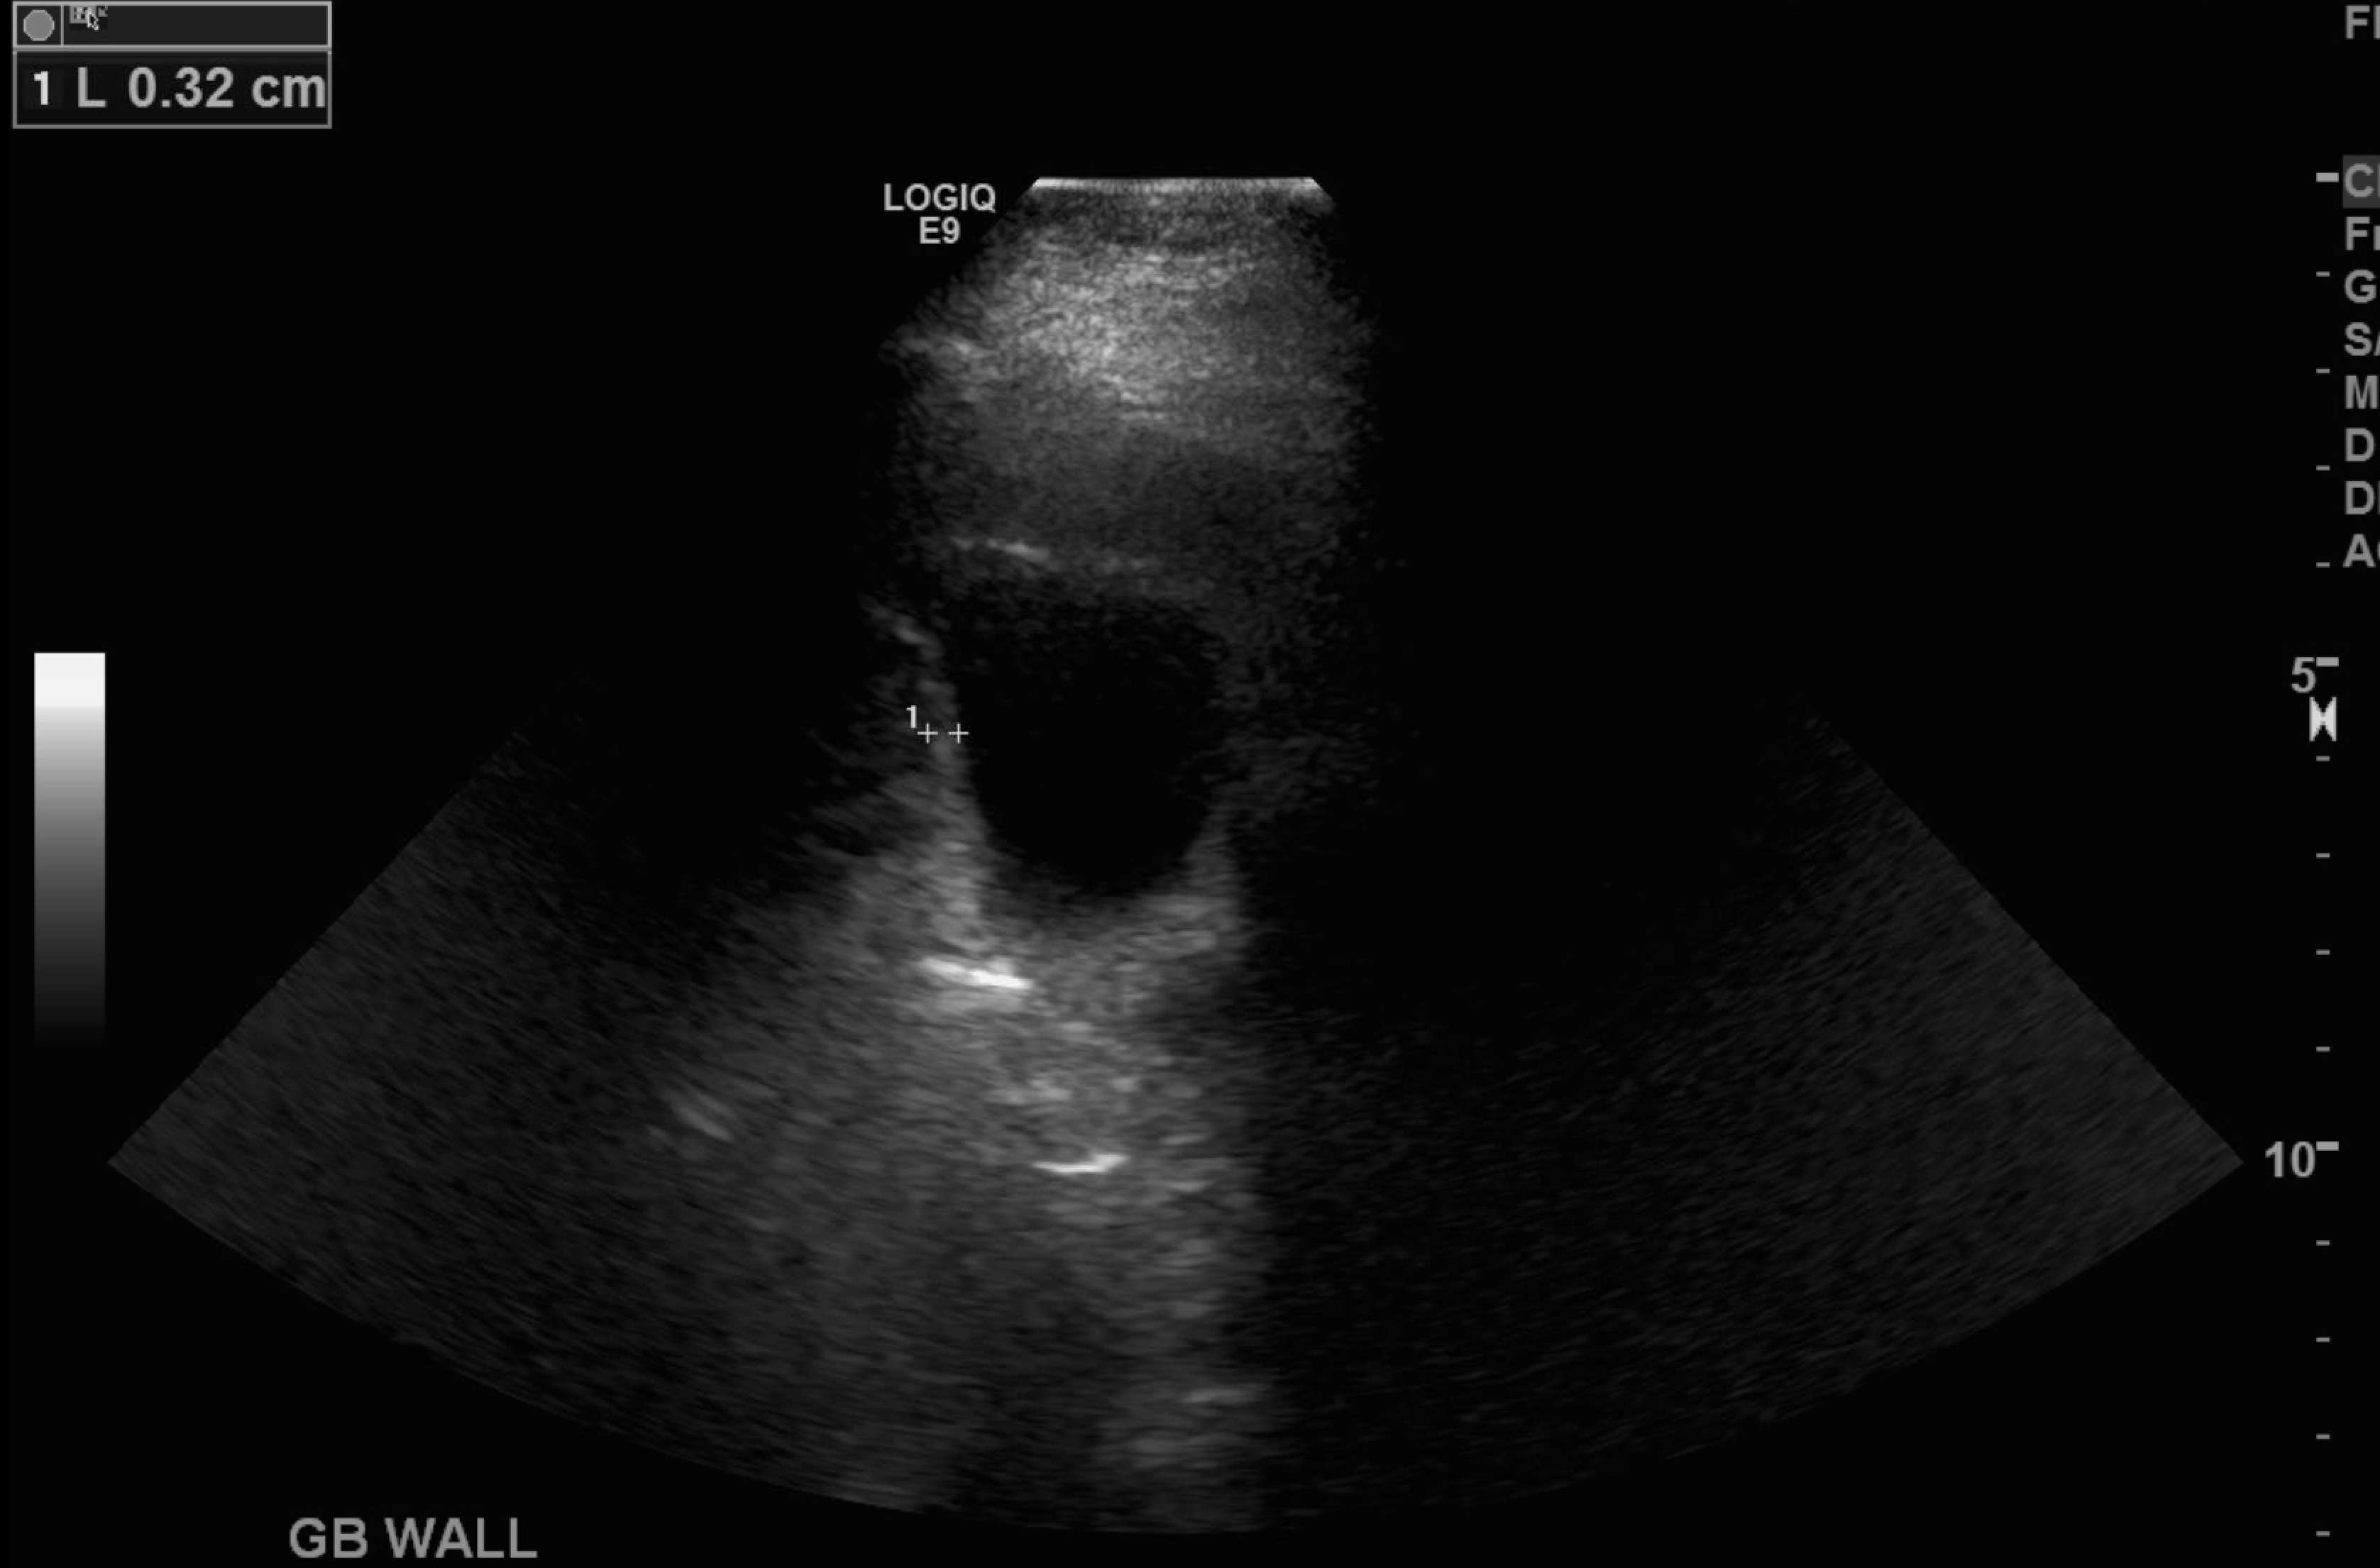

Age: 78

Sex: Female

Indication: Right upper quadrant pain

Radiotracer: Tc99m mebrofenin

Sample ReportNo evidence for acute cholecystitis. Patent biliary system.